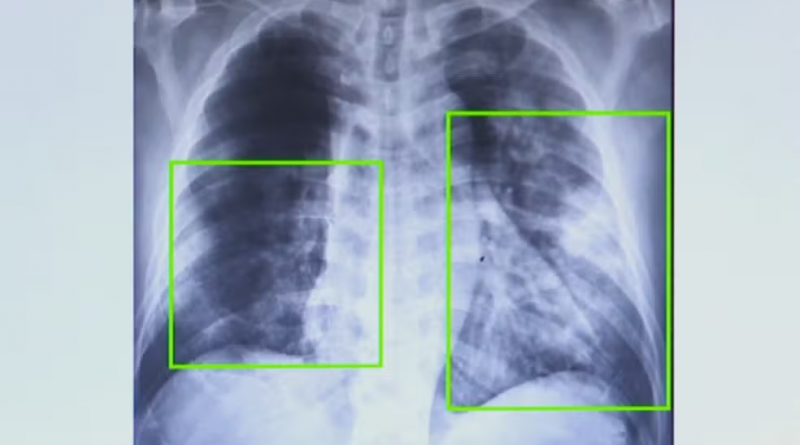

/i.s3.glbimg.com/v1/AUTH_59edd422c0c84a879bd37670ae4f538a/internal_photos/bs/2025/w/h/wH11UESdmfwtLhVFM50g/1.png)

Atendimentos por pneumonia quase dobram em 7 meses na região de Campinas. — Foto: Reprodução EPTV